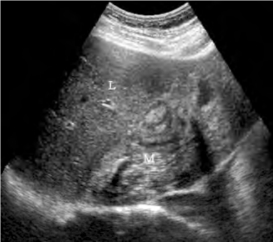

1.37.7七、卵巢囊性肿瘤